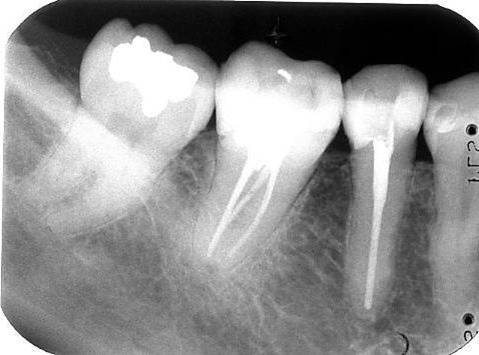

Een “C-shaped canal”

Een C-shaped canal komt af en toe voor bij de ondermolaren. Meer in de tweede ondermolaar dan in de eerste.

Herkenning is belangrijk omdat anders zoals altijd naar de 3 of 4 kanalen wordt gezocht die zich normaal in een ondermolaar bevinden. Uiteindelijk is dan een groot deel van het kanalensysteem niet gereinigd. Met een behandelmicroscoop valt onmiddellijk te zien dat het niet om normale kanalen gaat maar om een complex halve maanachtig systeem.

Goed preparen van een C-shaped canal is buitengewoon lastig. Het is handig om distolinguaal en mesiolinguaal eerst 2 kanalen te preparen. Dit kan op de gebruikelijke wijze zoals beschreven bij de primaire endodontische behandeling. Vervolgens kan op twee manieren verder worden gegaan. Op elke plaats waar een handvijl nog naar apicaal wil wordt opnieuw een kanaal geprepareerd. Uiteindelijk is het grootste deel van het complexe kanaalsysteem dan wel schoon geprepareerd. Een andere mogelijkheid is om vanuit de reeds geprepareerde 2 kanalen met ultrasone vijlen het gehele halve maan gebied te reinigen. Dit kan ook met behulp van Rotary shaping files. Ook Gates Glidden drills zijn erg handig om “de halve maan” te reinigen.

Vullen van het complexe kanalensysteem is het gemakkelijkst te doen met een combinatie van System B en Obtura II . De laterale condensatie techniek is hier minder geschikt.

Met System B worden de apicale delen van de kanalen gevuld en vervolgens wordt met de warme guttapercha spuittechniek van Obtura II de rest van het complexe systeem opgevuld.